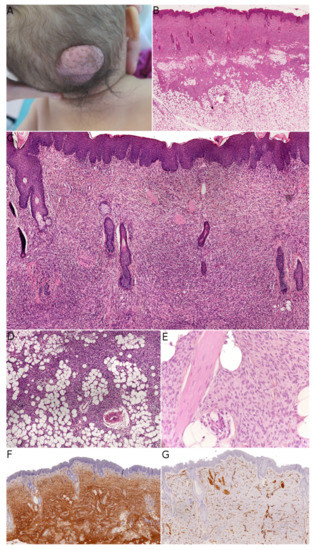

Figure 1. Fibroblastic connective tissue nevus. (A) Clinical presentation on the scalp of an infant (courtesy of the Department of Maxillofacial Surgery, Necker-Enfants Malades hospital, Paris, France). (B) Low-power view of the lesion showing infiltration of the dermis and subcutis (HE ×50). (C) Short intersecting fascicles surrounding the appendages and epidermal hyperplasia (HE ×100). (D) Extension into the subcutis (HE ×100). (E) High-power view showing the bland morphology of the spindle cells (HE ×200). (F) Diffuse positivity for CD34 (×50). (G) In this case, smooth muscle actin was negative, with internal controls on vessels and smooth muscles (×50).

Fibroblastic connective tissue nevus (FCTN) was described in 2012 in a series of 25 cases. This variant of connective tissue nevus has some clinical and histological particularities [3,8]. It typically appears during the first decade of life as a slowly growing, painless, plaque-like, or nodular skin lesion, and is mainly located on the trunk, head, and neck and less frequently on the limbs. Girls are more often affected than boys (sex ratio: 0.5–0.6). The lesions range from 0.18 to 2.0 cm in size, and FCTN is rarely diagnosed on the basis of clinical signs alone. Histologically, FCTN is a poorly circumscribed dermal lesion that arises in the reticular dermis and extends to the superficial subcutis. In 70% of cases, there is overlying papillomatosis of the epidermis. In about 60% of cases, abnormally superficial adipocytes are seen in the reticular dermis. The tumor is composed of short, intersecting fascicles of bland, spindle-shaped fibroblasts/myofibroblasts with weakly eosinophilic cytoplasm and elongated nuclei with no atypia and no mitoses. It extends between the collagen bundles, around the appendages and into the subcutaneous septa. The most useful immunostaining marker is CD34, which is positive in 87% of cases—albeit often weakly and in focal sites. Smooth muscle actin (SMA) is weakly and focally present in less than 50% of cases, and S100 is always absent (Figure 1).